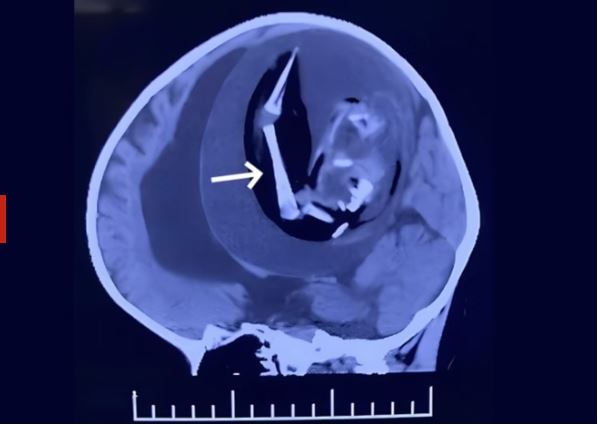

O feto, que media cerca de 18 centímetros e possuía braços, cabelos e olhos, estava alojado no crânio da menina desde o seu desenvolvimento no útero. A anomalia, que ocorre quando um embrião se desenvolve dentro do corpo de seu irmão gêmeo, é mais comum no abdômen, com apenas 200 casos documentados no mundo, sendo apenas 18 dentro do crânio.

Após exames detalhados que revelaram a presença de ossos na região, os médicos optaram pela cirurgia, o único tratamento possível para casos de FIF. Durante o procedimento, além do feto, foram encontrados diversos tumores ao redor do local onde ele estava alojado.